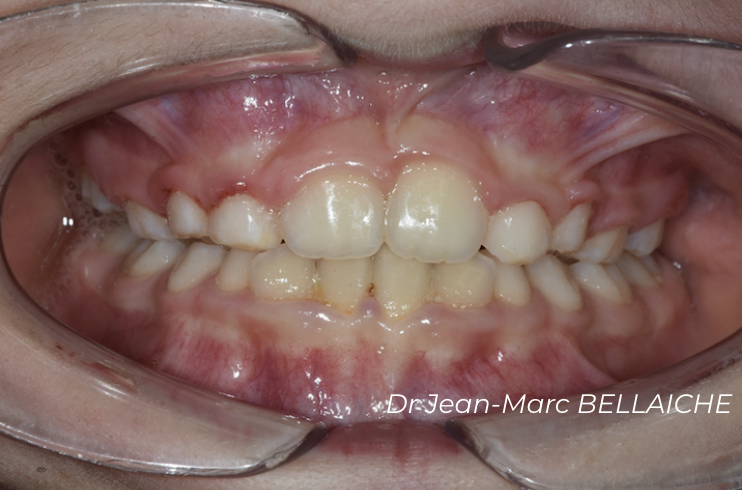

Cas 2 : Encombrement dentaire sévère

Situation "Avant Traitement" : cas d'encombrement associé à un recouvrement excessif des incisives supérieures sur les inférieures empêchant le déroulement normal des fonctions et pouvant être à l'origine de "déchaussements".